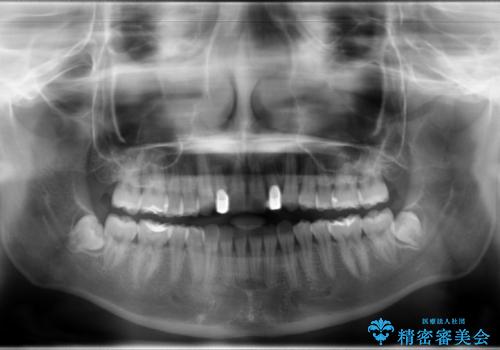

- ハーフリンガルシステムによる矯正治療を行いながら、スペースコントロールをみて前歯を仮歯へ

→矯正の終了をメドに仮歯をセラミックへ置き換える

かぶせ物の種類:PFZ standard